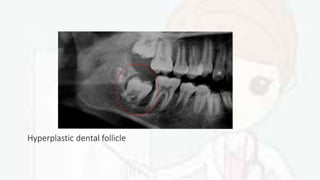

• Hyperplastic dental follicles have been reported with rough

hypoplastic amelogenesis imperfecta and in Lowe syndrome

Hyperplastic dental follicle